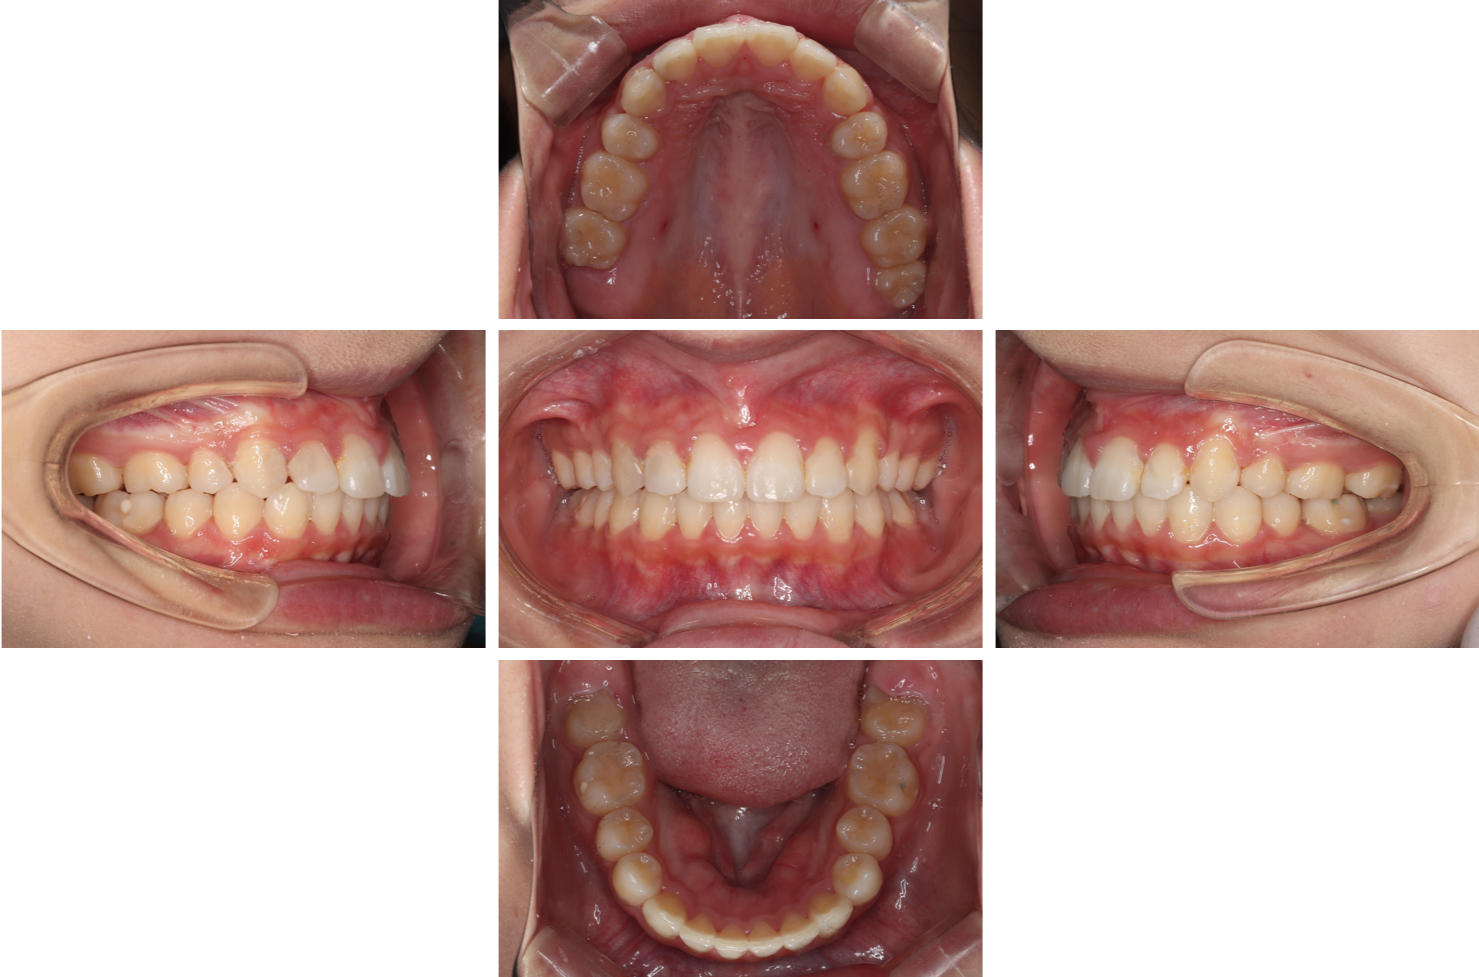

終了

終了して装置を外しました。

主訴である、上の前歯の突出を改善することができ理想的な咬合を獲得できました。

術後患者さんの笑顔も増えたと感じております。